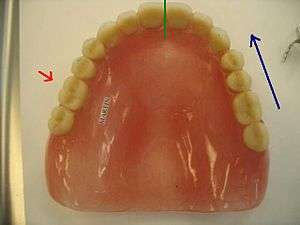

This photograph shows an occlusal view of a complete maxillary denture. The green line, indicating the dental midline, is the defining line when it comes to mesial-distal direction. The blue arrow, which indicates a mesial direction, applies to the opposite side as well up until the green line. The red arrow is directly buccal to the right first maxillary molar, and the name label for the patient (Martin) is embedded in the resin directly palatal to the same tooth.